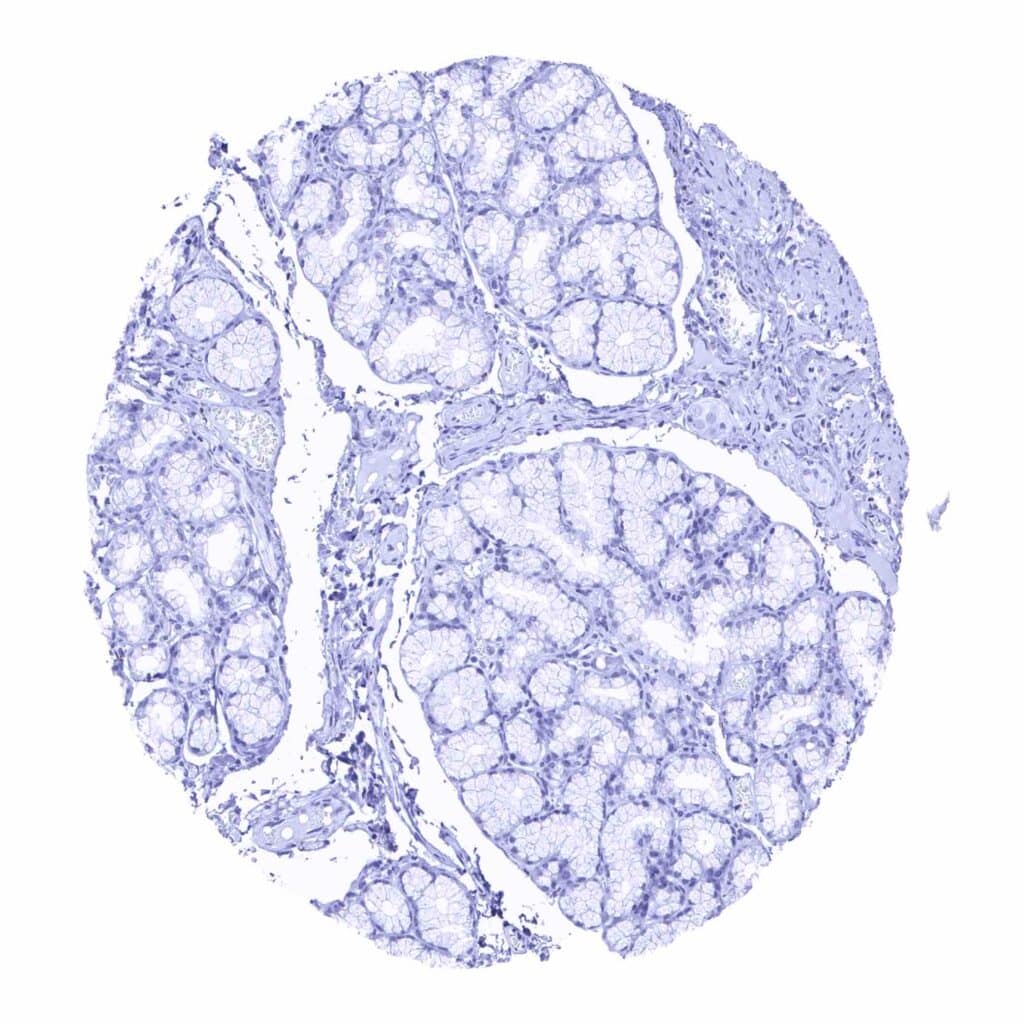

Pancreas – A weak, granular cytoplasmic prostein staining can be seen in a subset of pancreatic islet cells

Pancreas – Pancreatic islet cells are prostein negative in his sample